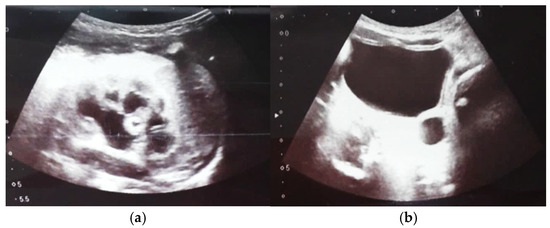

Figure 4. Ultrasound at 31st week of gestation. Bilateral hydrocalconephrosis.

Figure 5. Ultrasound at 32 weeks of gestation. Bilateral pyelectasis.

Our experience with congenital malformations of the urinary system refers to the following clinical case (Figure 2, Figure 3, Figure 4, Figure 5, Figure 6, Figure 7, Figure 8 and Figure 9). In the first case, during pregnancy, the 21-week ultrasound determined bilateral renal pyelectasia. The fetus had hydronephrosis on the right; at 31 weeks, it had bilateral hydrocalconephrosis; and at 32 weeks, bilateral pyelectasia. It suffered premature birth at 36 weeks, with complicated anomalies of the forces of contraction, prolonged birth, and birth weight of 2200 g. Postnatal ultrasonography was supplemented by intravenous urography, and bilateral hydronephrosis was determined. Hydrocalconephrosis on the left was discovered. The complete diagnosis was established: congenital renal malformation; bilateral pyelectasia; bilateral hydronephrosis; hydrocalconephrosis on the left; and severe reduced glomerular filtration rate (GFR), GFR > 2SD below mean.